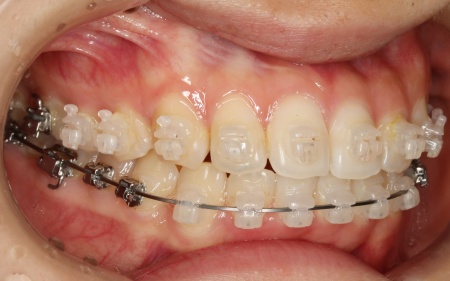

歯の表面にブラケットと呼ばれるボタン状の装置を接着し、そこにワイヤーを通して歯を移動させる方法です。

患者様は目立たない治療方法を望まれていたため、ブラケットには白く目立ちにくい「セラミックブラケット」を選択しました。

まずは歯の表面にセラミックブラケットを装着し、ワイヤー矯正で歯を全体的に移動させます。

歯並びがある程度正しい位置に並んだら、マウスピース矯正で微調整を行いました。